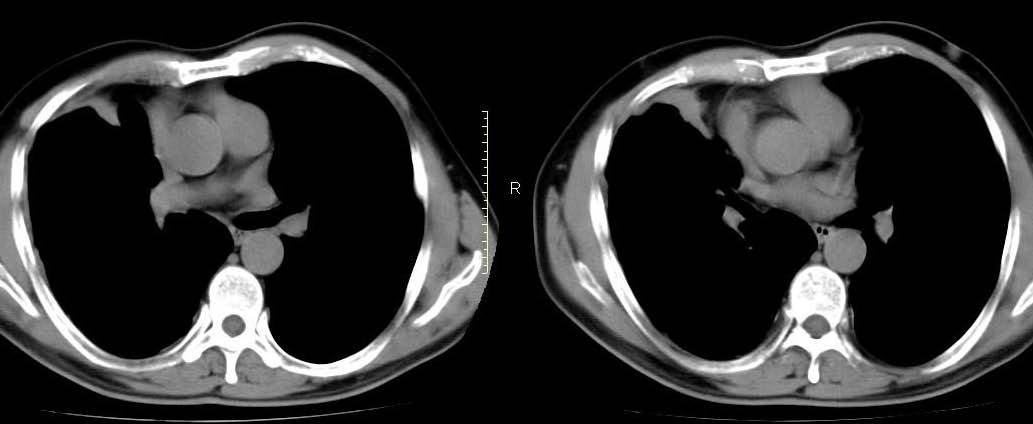

男,56岁,右侧腋窝下巨大软组织包块转移。欢迎讨论。

该病例为已经确诊的右侧恶性胸膜间皮瘤病例,有青石棉接触史,早期就是胸水,右侧胸壁“花边状改变”,心隔角区软组织阴影形成。近期右侧腋窝下巨大软组织包块,病检为转移瘤。图片没有完全考来,主要是给大家看一下胸膜间皮瘤的病例。,右侧

右侧腋窝下巨大软组织包块已经被切除后的ct片,该病例有多家医院较多的ct检查片。

右心膈角区一不规则肿块伴相邻胸膜不规则增厚,考虑胸膜间皮瘤(恶性)?右肺中叶内侧段肺癌?建议穿刺活检。